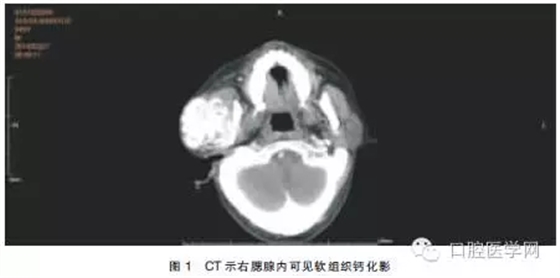

查體:患者面形左右不對(duì)稱,右耳前有一約5.0 cm×5.0 cm大小的軟組織隆起,質(zhì)地較硬,與周圍組織界限不清,無活動(dòng)度,開口度未受影響。血鈣:2.7mmol/L,血磷:2.9mmol/L,肌酐:953μmol/L,尿素氮:5.7mmol/L。使用GE VCT64排螺旋CT進(jìn)行掃描(球管電流:250mA,掃描電壓:120kV,周期:0.4s/周,層厚:5mm),掃描范圍:顱底至頸根部。結(jié)果示:右腮腺區(qū)見團(tuán)塊狀混雜密度(軟組織內(nèi)伴鈣化)影,邊界欠清,與腮腺組織及血管分界不清,與咬肌及周圍骨結(jié)構(gòu)分界欠清(圖1)。